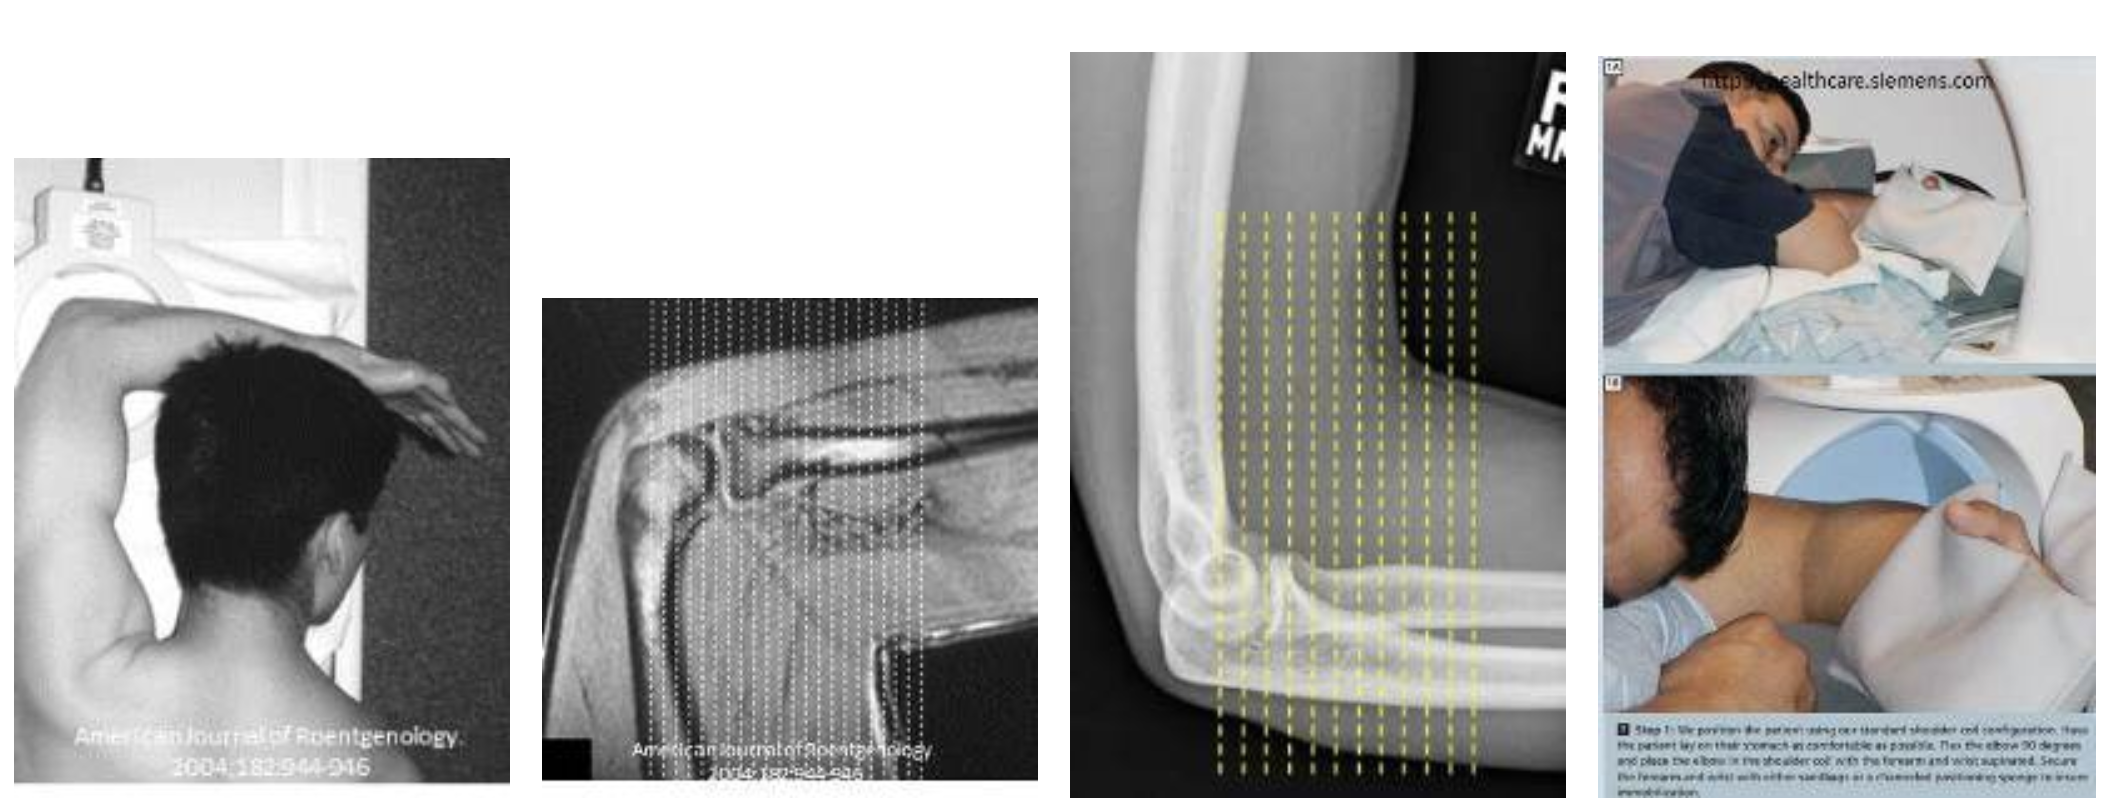

- Flexion, Abduction, Supination

- For better visualization of distal biceps tendon

- After usual sequences, place arm as shown (supination of wrist is important!)

- Images are oriented perpendicular to radius

- Images will be coronal to humerus but sagittal to rest of body